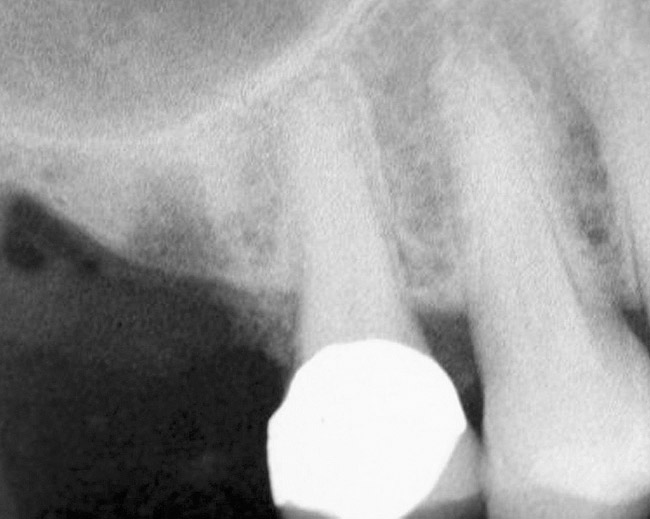

Accidental Penetration of Sinus Membrane with First Twist Drill

When using a 2-mm twist drill, the sinus could inadvertently be entered. This incursion can be verified by occluding the patient's nostrils and having the patient blow (Valsalva maneuver). If the membrane has been perforated, air bubbles will appear in the osteotomy. Some clinicans indicate that if a perforation has occurred, the sinus floor elevation procedure should be aborted and the site should be allowed to heal for 4 weeks and then redone.4 However, the situation may be salvageable (Figure 12, Figure 13, Figure 14, Figure 15). The amount of bone that is subantral can be re-evaluated, and then the second drill (eg, 2.8-mm wide) used, making sure not to enter the sinus. Similarly, the third drill (3.5-mm wide) can be used to proceed 1 mm short of the sinus floor. The initial sequence should be followed with respect to adding bone; whether or not a dome has formed should be verified radiographically. If the graft material is contained, then the procedure can be brought to conclusion as if a perforation had not occurred. On the other hand, if the material was not contained, it may appear on the radiograph as a "trail of smoke." In this case the procedure needs to be aborted or a lateral wall sinus lift needs to be performed to complete the task and repair the perforated membrane. In general, the ostium is 2.4-mm wide;33 it ranges from 2.14 mm to 6.77 mm.34 Therefore, particles that have escaped through the membrane will probably be swept through the ostium by the ciliated columnar epithelium without any untoward occurrence. Other authors have also noted that a perforation of the membrane does not necessarily result in failure of an implant that penetrates into the sinus.35

Figure 12  Initial radiograph at site No. 3.

Figure 12

Figure 13  Despite initial perforation into the sinus with the 2.1-mm twist drill, the drilling sequence was continued after the drill depth was adjusted to be 1 mm short of the subantral floor. The radiograph demonstrates that after the subantral floor was up-fractured and bone was added via the osteotomy, the initial puff of bone was contained. Therefore, the procedure could continue.

Figure 13

Figure 14  Additional bone was added via the osteotomy.

Figure 14

Figure 15  Implant successfully placed.

Figure 15